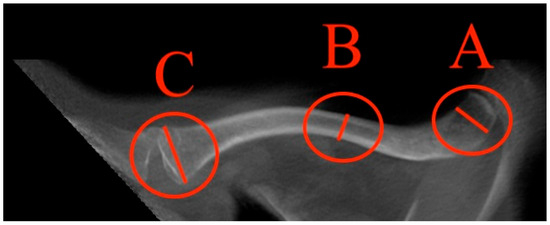

- Max. medial diameter: The distance was measured by drawing a line between the most dorsal and the most ventral points of the medial end of the clavicle (Figure 5).

- Min. diameter: The distance was measured by drawing a line between the least ventral and least dorsal points of the clavicle (Figure 6).

- Max. lateral diameter: The distance was measured by drawing a line between the most ventral and most dorsal points of the lateral clavicula (Figure 7).